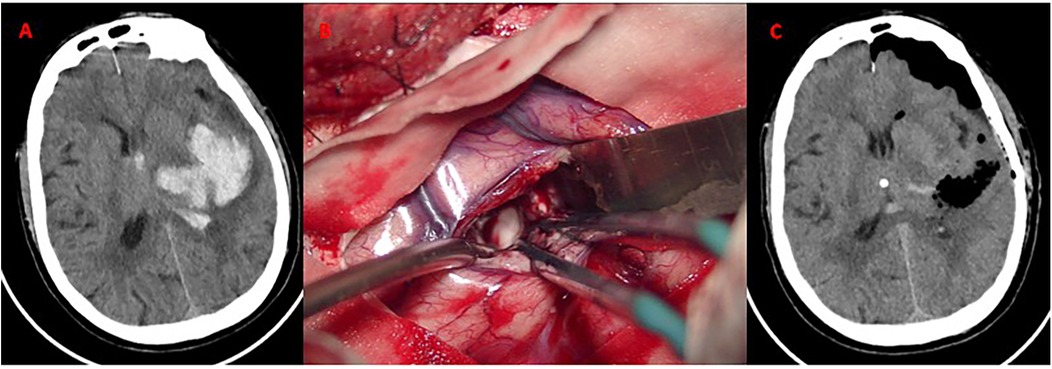

Panel A shows a CT scan of the brain with a bright irregular area indicating hemorrhage. Panel B captures a surgical procedure on brain tissue with visible blood vessels and instruments. Panel C displays a post-operative CT scan with reduced hemorrhage and dark areas indicating possible air or fluid collection.

Figure 4. Craniotomy evacuation of left basal ganglia hematoma. (A) Axial CT demonstrates acute hypertensive hemorrhage (volume: 30 mL) in the left basal ganglia; (B) Intraoperative microscopic view. Hematoma evacuation via a standard trauma craniotomy (6 × 8 cm bone flap). The bone flap was successfully repositioned without decompressive craniectomy. (C) CT confirms near-total hematoma evacuation. No new ischemic lesions or rebleeding observed.